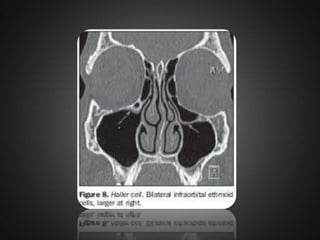

• 24.

Haller cell  Infraorbitalethmoid cells or Haller cellsare ethmoid air cells located anteriorly to the ethmoid bulla, along the orbital floor, adjacent to the natural ostium of the maxillary sinus, which may cause mucociliary drainage obstruction, predisposing to the development of sinusitis.